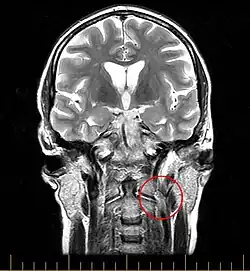

Chronische Cerebro-Spinale Venöse Insuffizienz (CCSVI) ist ein Syndrom, bei dem die Hals- und Thoraxvenen nicht in der Lage sind, das Blut effizient aus dem zentralen Nervensystem (ZNS) abzuleiten. Es wird vermutet, dass dies durch Stenosen (Verengungen) der Vena jugularis interna und/oder der Vena azygos hervorgerufen wird. Ein solches „System“ wurde von Paolo Zamboni 2008 beschrieben. Er propagierte auch einen möglichen Zusammenhang von CCSVI mit der Multiplen Sklerose (MS), eine Hypothese, die bereits ab den 1930er Jahren diskutiert wurde. Ein kausaler Zusammenhang mit der Multiplen Sklerose konnte nicht nachgewiesen werden. In einer relativ kleinen Studie Zambonis (300 Teilnehmer), wurde das Syndrom bei allen MS-Patienten gefunden, jedoch bei keiner Kontrollperson.[1] CCSVI wurde 2009 als vaskuläre Fehlbildung klassifiziert.[2]

Die zuverlässigste Untersuchungsmethode um CCSVI festzustellen ist eine Katheter-Venographie. Allerdings ist diese mit einem relativ hohen Aufwand an Ressourcen verbunden und bringt für den Patienten eine nicht unerhebliche Strahlenbelastung mit sich. Deshalb wird in aller Regel davor eine Voruntersuchung mittels Magnetresonanz-Venographie sowie eine extra- und transkranielle Doppler-Sonographie[1] durchgeführt. Nur falls diese Voruntersuchungen einen hinreichenden Verdacht auf pathologische Veränderung der Venen geben, wird anschließend die Katheter-Venographie durchgeführt.

Die Theorie eines Zusammenhangs von CCSVI und Multiple Sklerose geht davon aus, dass es, bedingt durch unterschiedliche Fehlbildungen der drainierenden Blutgefäße, zu einem Rückfluss von Blut ins ZNS kommt und es dadurch zu erhöhten Ablagerungen von neurotoxischem Eisen im Gehirn kommt. Diese Ablagerungen und der durch sie herbeigeführte Zelluntergang löse die für die MS typischen Autoimmun-Reaktionen aus. Auf der Grundlage diese Theorie wurden im Rahmen einer Studie 65 MS-Patienten experimentell mittels Ballondilatation behandelt.[11]